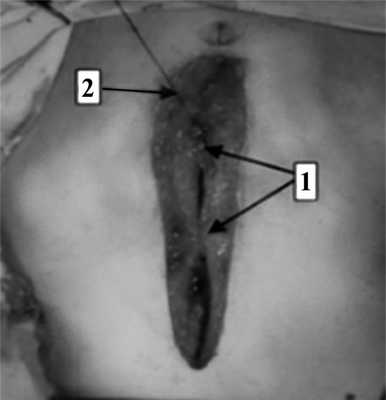

На следующем этапе, после проведения обучения, новый способ лапарорафии внедрили в клиническую практику (рис. 3). Рис. 3. Ушивание лапаротомной раны (интраоперационная фотография). 1 — наложены укрепляющие швы; 2 — наложение непрерывного шахматного шва.